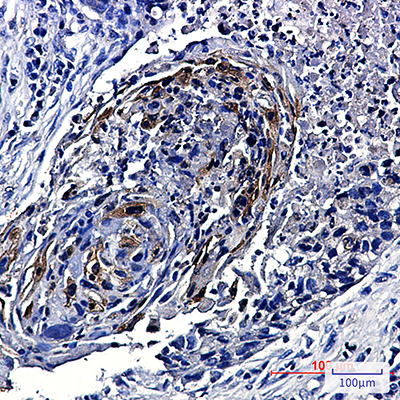

WB,IHC-P

WB: 1:500-1:1000 IHC: 1:50-1:100